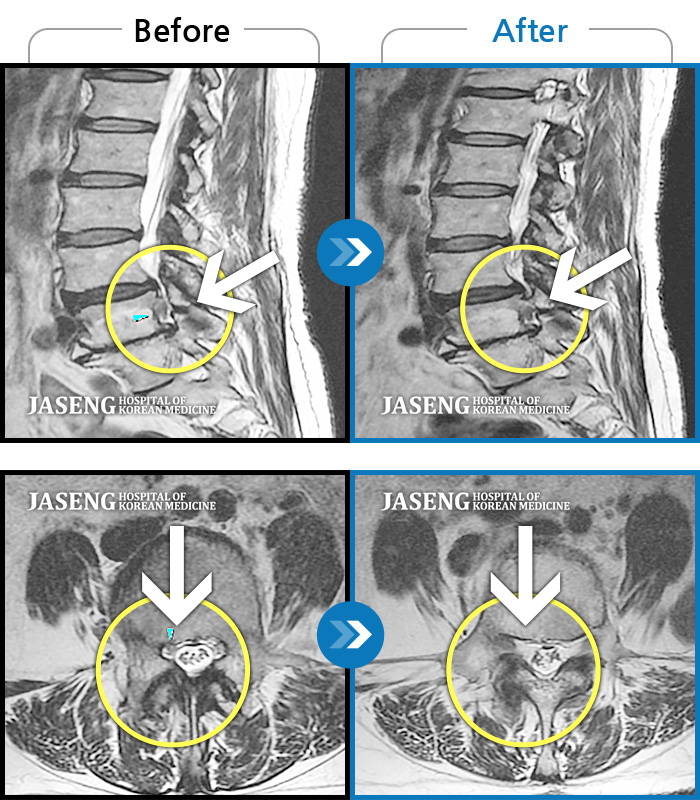

허리디스크

보라매 · 왕오호 원장

허리와 좌측 엉치 통증

촬영시기

2015.12.29 ~ 2018.10.11

2018.12.28